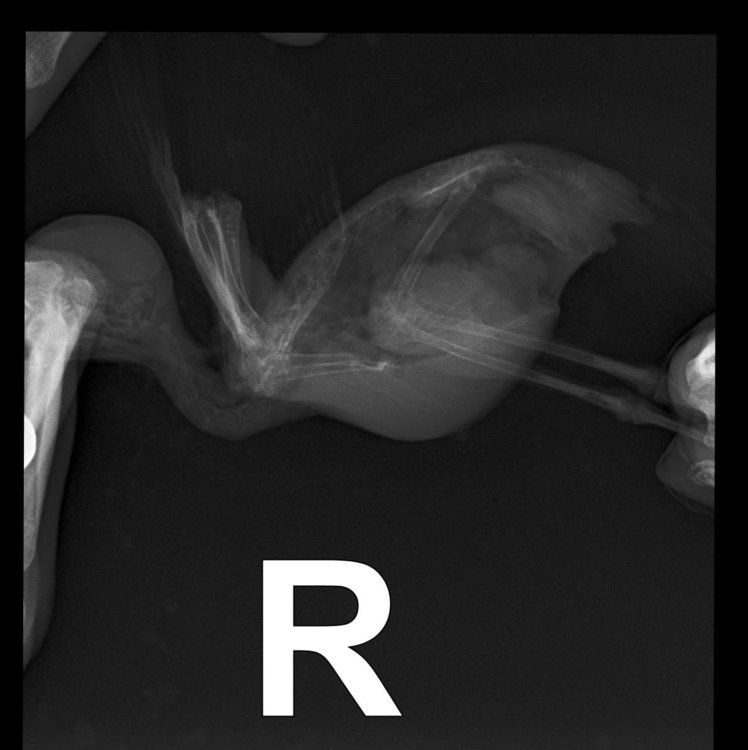

Необходима консультация. Попугай какарик (самка) стала себя странно вести, пропала активность, сидит в темных местах, и перестала летать.

Были на приёме у орнитолога, по внешнему осмотру птица здорова, направили на рентген.

Рентгеновский снимок прислали, но без заключения, в ходе телефонного разговора с орнитологом оказалось, что имеется кистозное образование и недостаток кальция, из лечения был прописан мелоксидол и кальций.

Скажите пожалуйста, что это за образование и насколько все серьезно?

Орнитолог сказал, что пока просто наблюдение. Очень переживаю, возможно кто-нибудь сможет расшифровать снимок и высказать своё мнение.

( после приема лекарств птица практически такая же активная, как и была, летает, но довольно редко)

045B5C80-1583-4399-AD63-CCF6F44A0716.jpeg